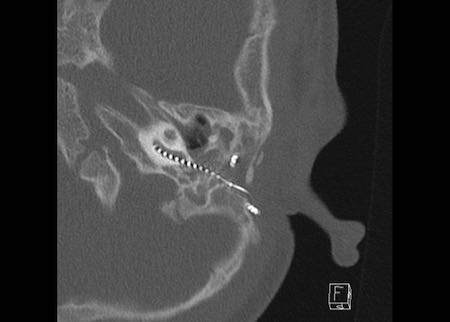

Ca lâm sàng 2

Các hình ảnh này cho thấy một điện cực cấy ghép bị lạc chỗ.

Điện cực ốc tai được đưa vào phía dưới vòng đáy của ốc tai và kết thúc ở vùng hạch gối (geniculate ganglion).